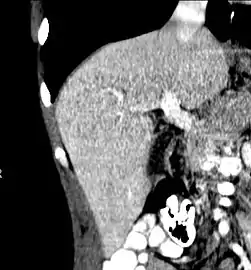

Left lobe liver tumor

The liver is a vital organ and supports almost every other organ in the body. Because of its strategic location and multidimensional functions, the liver is prone to many diseases.[52] The bare area of the liver is a site that is vulnerable to the passing of infection from the abdominal cavity to the thoracic cavity. Liver diseases may be diagnosed by liver function tests–blood tests that can identify various markers. For example, acute-phase reactants are produced by the liver in response to injury or inflammation.

After resection of left lobe liver tumor

Liver transplantation is the only option for those with irreversible liver failure. Most transplants are done for chronic liver diseases leading to cirrhosis, such as chronic hepatitis C, alcoholism, and autoimmune hepatitis. Less commonly, liver transplantation is done for fulminant hepatic failure, in which liver failure occurs rapidly over a period of days or weeks.